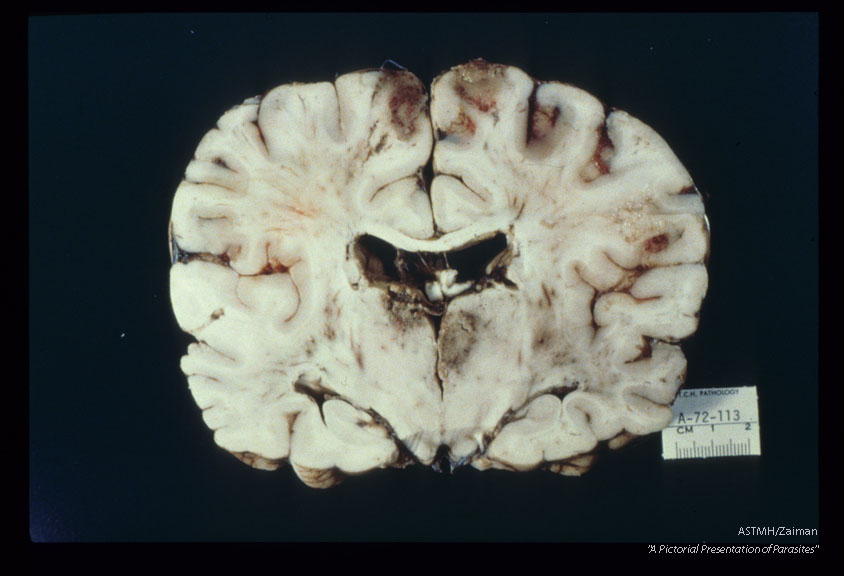

Fatal case with uveitis and meningoencephalitis. Gross pathology.

Acanthamoeba

Description: Fatal case with uveitis and meningoencephalitis. Gross pathology.